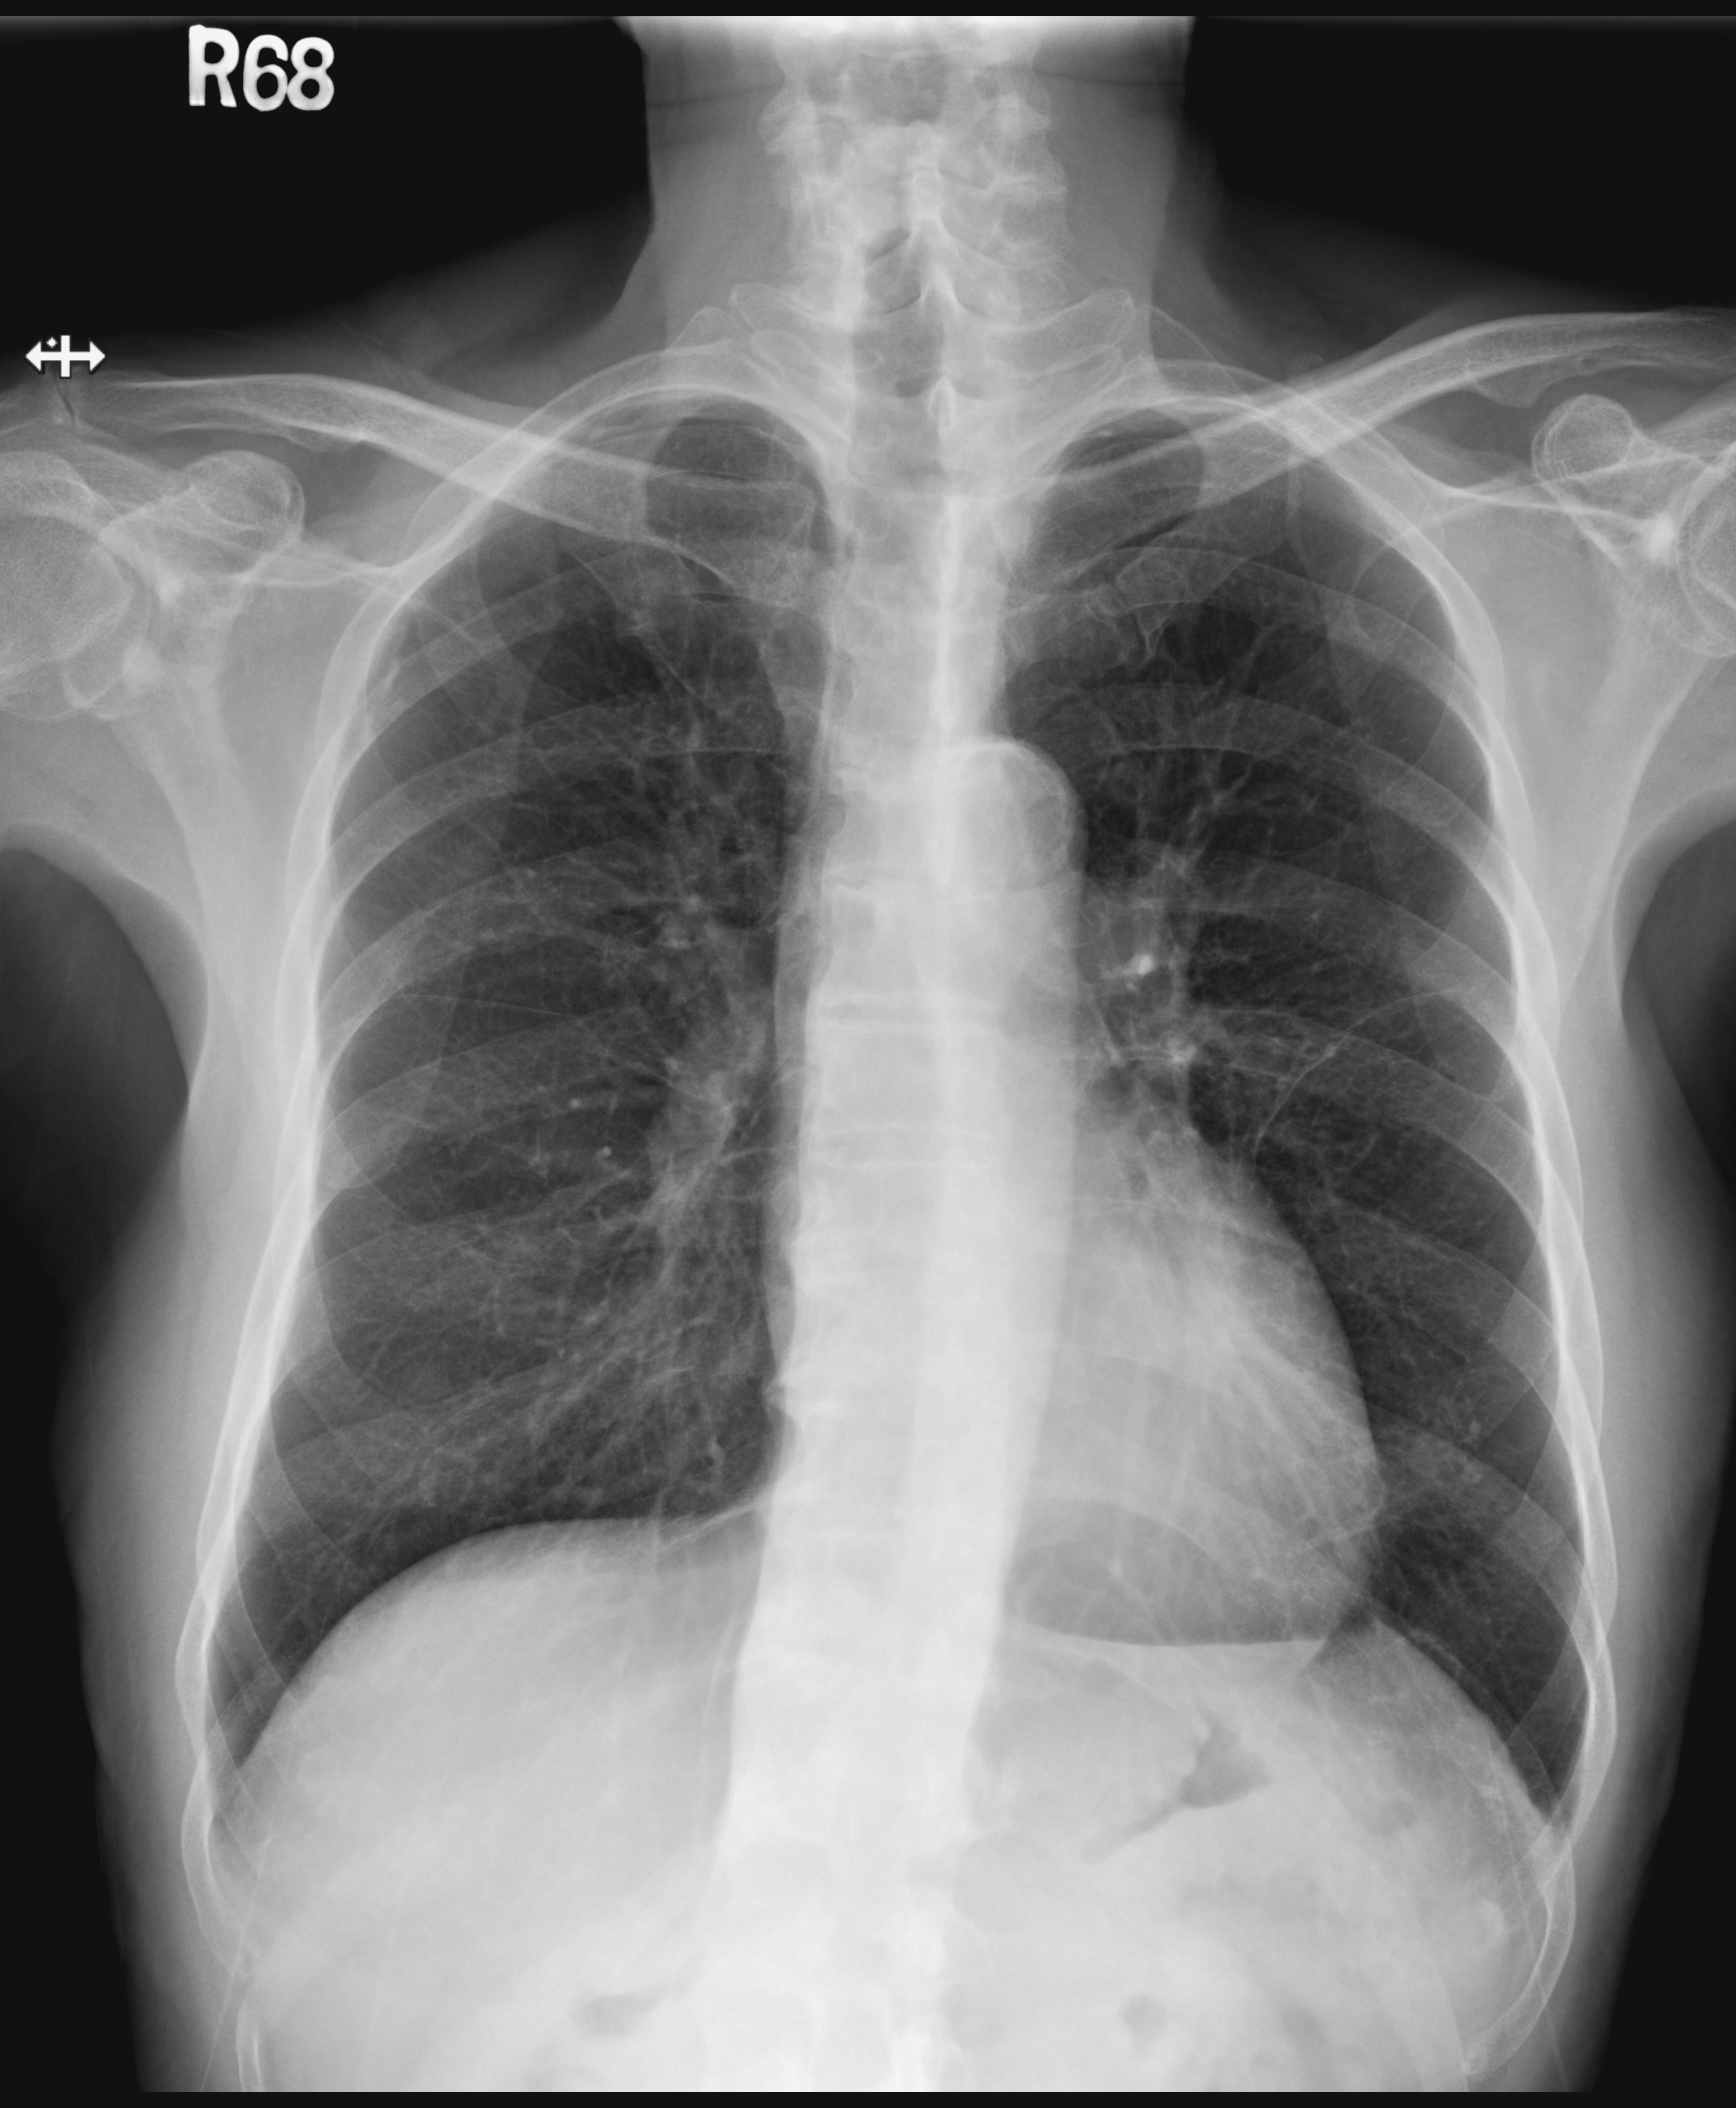

Lab data showed fair renal function and mild anemia. Chest X ray found no cardiomegaly or pulmonary congestion. ECG showed persistent ST elevation over anterior leads. Echocardiogram disclosed general LV hypokinesia with reduced LVEF about 30% and LV aneurysm formation.